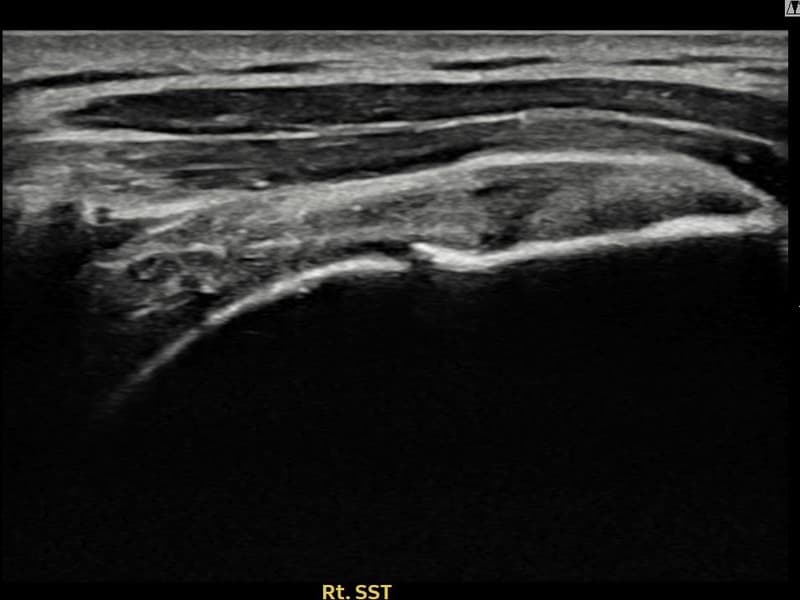

After

시술 전 초음파 측정 결과 파열 크기는 9mm × 4mm (힘줄 두께의 약 38% 결손)로 확인되었습니다. 시술 전 초음파에서 우측 극상근건 내 에코 단절과 함께 건내 고에코 석회화 소견이 동반 확인되었습니다. 시술 후 초음파에서 파열 부위의 연속성이 회복되고 석회화 부위의 에코 패턴이 개선된 것이 관찰되었습니다.

50대 후반 여성 환자분으로, 야간 통증이 극심하여 어깨를 아래로 향하고 자도 통증이 느껴지는 상태로 내원하셨습니다. 초음파 검사에서 극상근건 부분파열과 함께 건내 석회화가 동반된 복합 소견이 확인되었습니다. 석회화와 파열이 함께 존재하는 경우 충격파만으로는 힘줄 구조 회복이 어려워 초음파 유도 하 축소봉합술을 선택하였습니다. 시술은 30여 분에 완료되었고 당일 귀가 가능하셨으며, 이후 보조기를 착용하며 단계적 재활을 진행하였습니다. 시술 11주 후 추적 초음파에서 파열 부위 연속성 회복과 함께 석회화 소견도 뚜렷이 감소한 것이 확인되어 야간 통증 없이 정상 생활에 복귀하셨습니다.